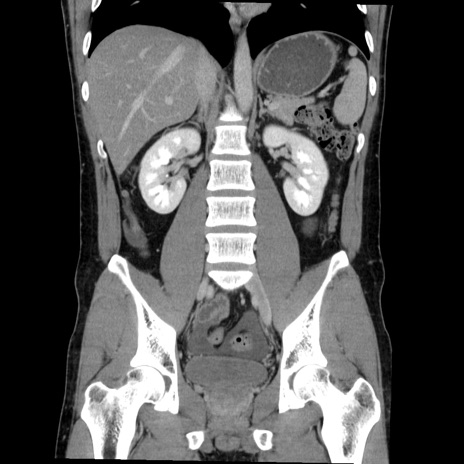

症例36(冠状断像)

【症例】20歳代 男性

【主訴】心窩部痛

【現病歴】今朝より上腹部痛あり。一旦軽快していたが再度出現したため救急要請。昨日夕に白身の魚を含む刺身を食べた。

【身体所見】BP 136/89mmHg、HR 74/min、BT 37.0℃、腹部:膨満、軟、心窩部に圧痛あり。反跳痛なし、筋性防御なし、腸雑音やや亢進あり。

【データ】WBC 17700、CRP 0.48